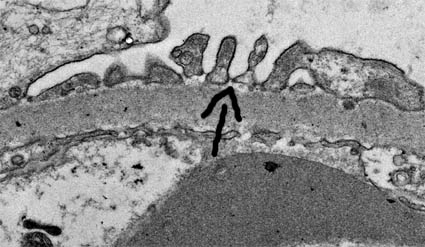

Figure 10c. Electron microscopy. podocyte processes are more clearly identified. One slit-diaphragm is marked with the arrow. Foot process effacement is a common feature in any cause of nephrotic syndrome, although it is the main alteration in minimal change disease. Slit-diaphram is anchored to the cytoskeleton of the podocyte, and there are many protein that are very important to the normal function (nephrin, podocyn, CD2AP, NEPH1, NEPH2, and so on; see the chapters on focal segmental glomerulosclerosis and minimal change disease).